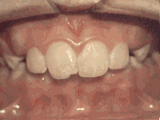

Deep overbite: Lower front teeth bite into palate

This adult patient (age twenty-five) required braces and jaw surgery to correct his severe overbite, with treatment taking two years. His problem could have been corrected without surgery if he had been treated before he was a teenager.